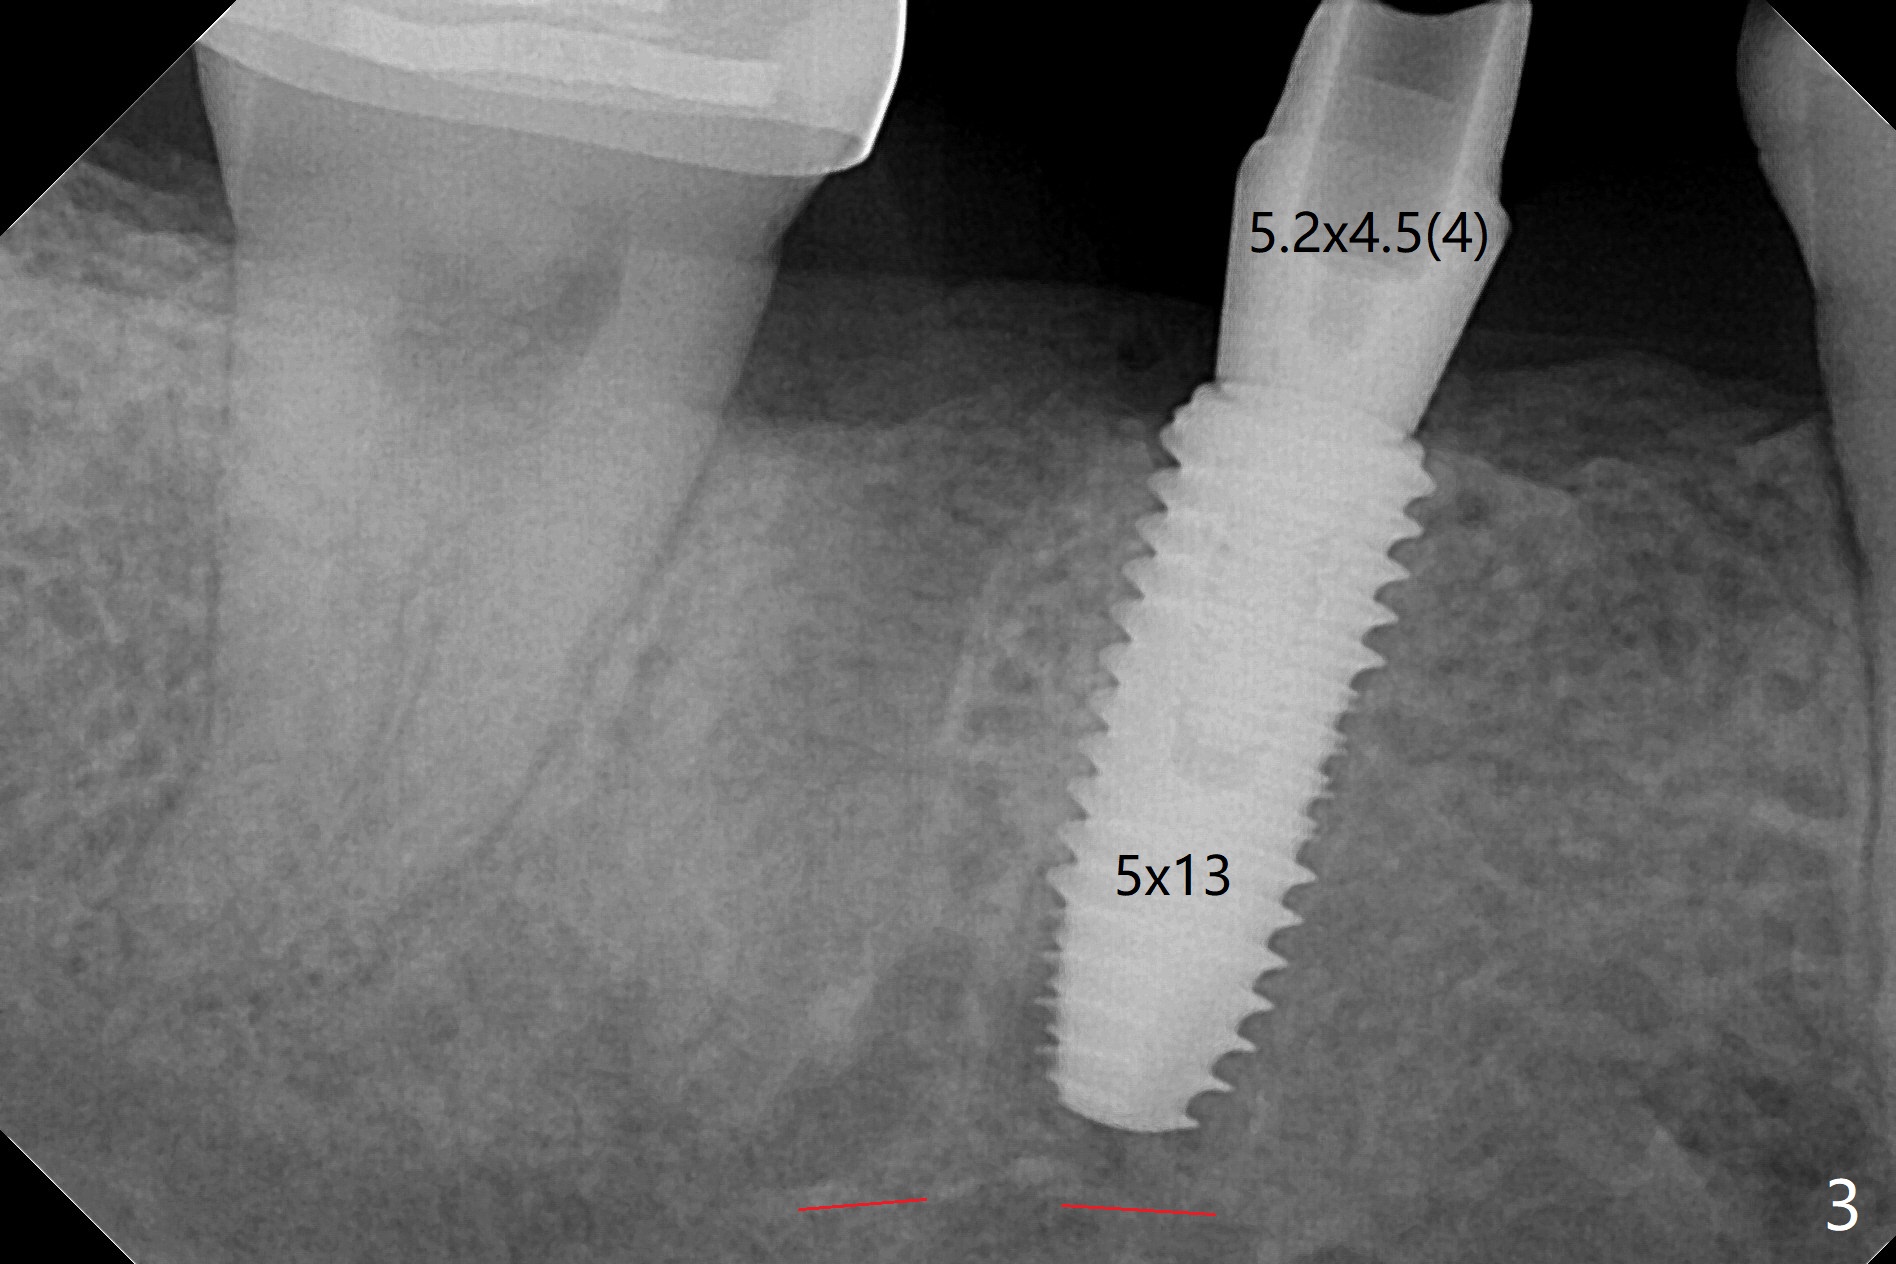

35岁男牙齿矫正后2年5个月右下6远中深龋,拔除后,近中根尖肉芽组织(图零(术前CT冠状切面):*)刮除疼痛,必须阻滞麻醉才能控制疼痛,可能与下牙槽神经分支(图零:红箭头)有关。原先准备在近中牙槽窝近中种植(5x11.5mm),术中发现近中牙槽窝种植好像方便,位置不错,不由自主在那里开始钻洞,由于牙槽窝深,钻洞必须13毫米(图一(接近神经:红虚线)),之后发现钻洞(图二(术前CT3D长轴切面(黑色:近中,远中牙槽窝)):红圆圈)不够理想,使用Lindamann Bur将钻洞往颊侧近中移动(图二:箭头),最终在这方面结果可以(图三,三’,四),虽然接近神经,术后没有神经麻痹。放置粘性骨粉(图四:*),PRF膜,4-0 PGA缝线(图五),最后使用树脂敷料(图六:A)。后牙垂直空间少,术后一周需要降低树脂敷料高度(图七)。术后一个月取出敷料,牙槽窝愈合,植体平台远中稍微暴露(图八),准备一个月后制作临时牙冠。术后两个月植体远中没有暴露,但是基台远中边缘太高了(图九:>),换成6x4毫米愈合基台。下个月换成袖短的修复性基台,安置临时牙冠,牵拉7。舌侧cleats之间放置power chains,颊侧power hooks。其实术后4个月安置临时牙冠和band(图十),牙冠牙合面加高,这样7可以无阻挡移动(图十一:*;16x22 arch wire)。7远中放置power hook行不通,因为末端碰到颊侧前庭牙龈,造成创伤。只好用7颊侧原有牵引勾,在6近中安置一个短的power post (? 图十:箭头),按常规post往下,之间放置12毫米closed spring。如果post往上安置,7牙根牵引可能更有效?近中牵引一个月,第二磨牙前移大约2毫米(图十二:^),稍微近中倾斜,closed spring从12毫米更换到9毫米,舌侧换新的power chains x 4。下一个预约,用sensor 1拍摄根尖片证实第二磨牙近中倾斜,然后在它远中16x22钢丝安放power hook,下缘向颊侧弯曲,避免接触接触粘膜。